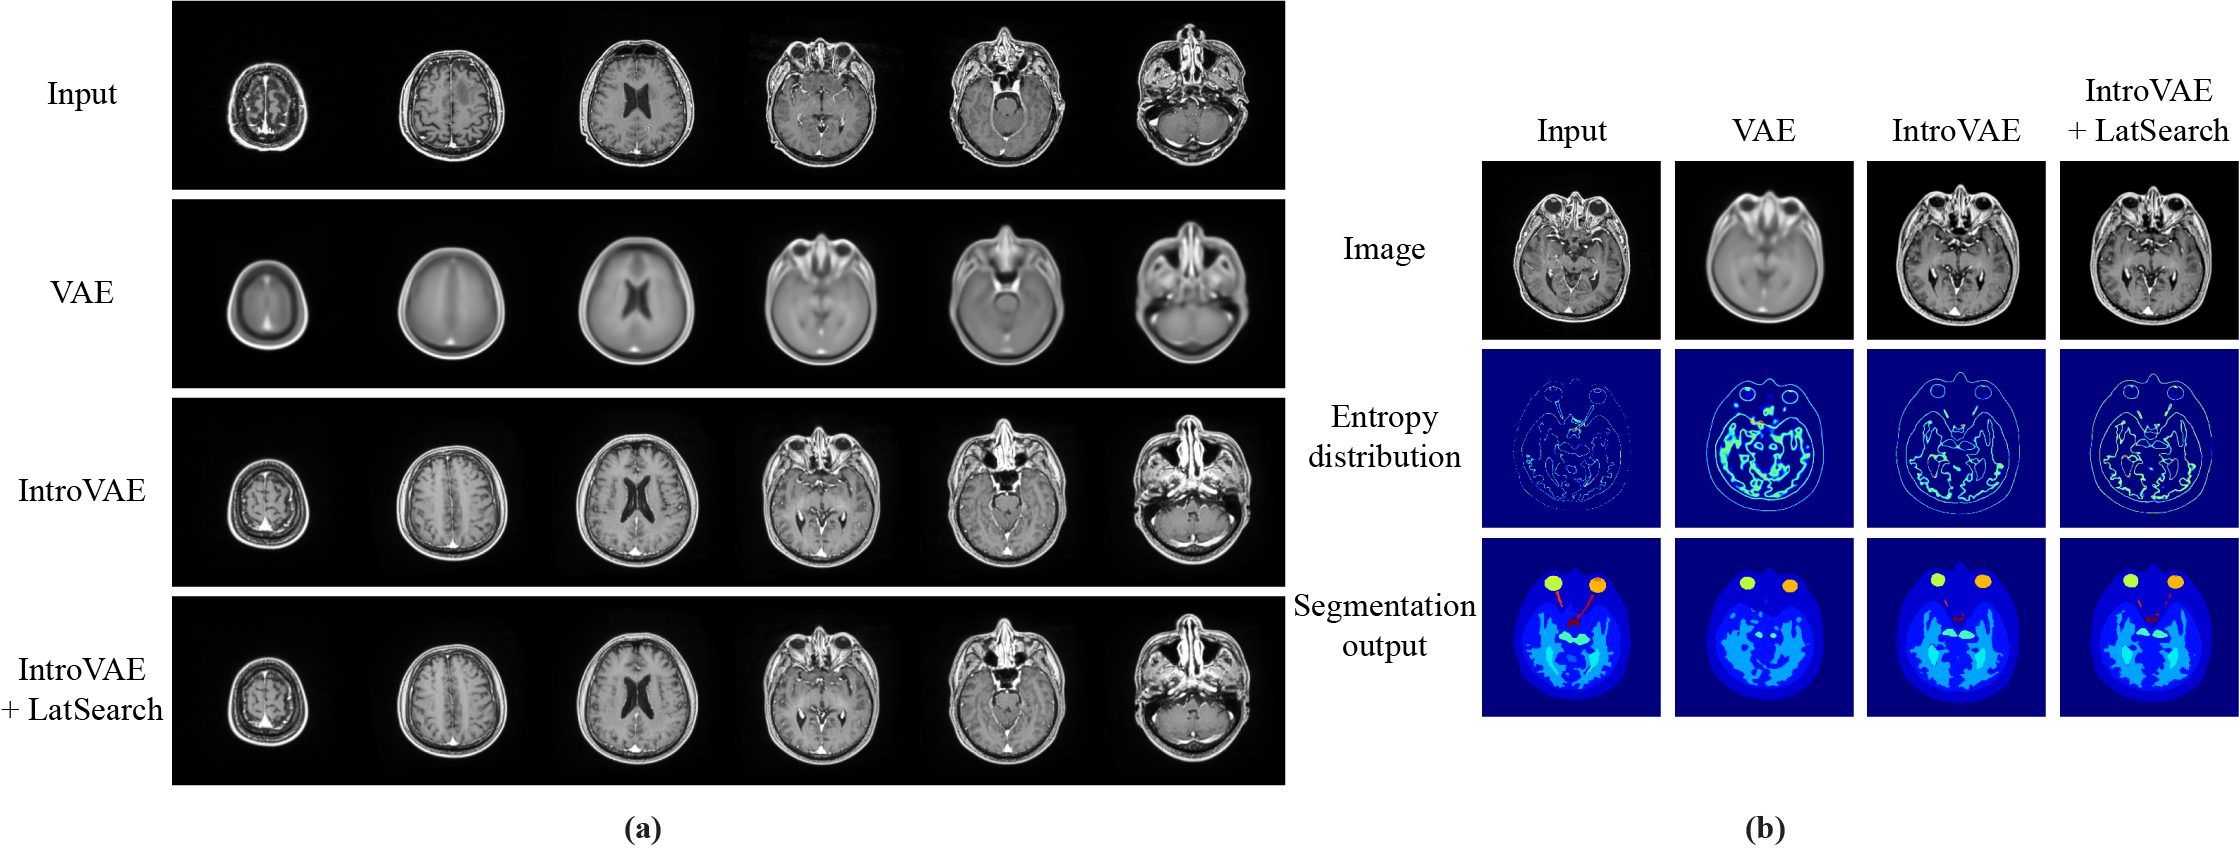

IV-B Training Results of Image Reconstruction Networks

Fig. 4a shows the sample training results for image reconstruction based on the training dataset. The first row shows the input images, and the second, third, and forth rows show the reconstructed images obtained using VAE, IntroVAE, and IntroVAE+LatSearch, respectively. Even after sufficient training steps, the images generated using VAE tended to be blurry, and the details of the input images were not reproduced. Meanwhile, IntroVAE and IntroVAE+LatSearch generated more realistic-appearing images with detailed structural information.

The pixel-wise softmax entropy was acquired from the segmentation network to evaluate the quality score. As demonstrated in Fig. 4b, the images generated by the VAE were blurrier than those yielded by IntroVAE, thereby generating disturbed segmentation outputs in accordance with the localization of higher entropy values. The mean standard deviations of the quality score were , , and for the VAE, IntroVAE, and IntroVAE+LatSearch, respectively, showing the highest value for IntroVAE+LatSearch.

To calculate the overlap score, the segmentation results for the input and reconstructed images were compared for each anatomical label. The mean standard deviations of the overlap scores were , , and for the VAE, IntroVAE, and IntroVAE+LatSearch, respectively. The highest value of the overlap score was also observed for IntroVAE+LatSearch.

Fig. 6 shows the rectified ROC curves, which were calculated by considering the voxels inside the body only. The detection performance (mean standard deviation) based on the rectified ROC–AUCs is summarized in Table I. It can be seen that metastatic brain tumor and postoperative cavity were detected with a sufficient ROC–AUC exceeding 0.7. Between these two classes, IntroVAE+LatSearch outperformed the other two image reconstruction networks, namely VAE and IntroVAE, where the order of the higher detectability was compatible with the higher anatomical fidelity. Meanwhile, we discovered a low precision due to the much higher prevalence of “normal” voxels over “abnormal” voxels; this can yield a larger number of false-positive voxels.

Finally, the visual examples are shown in Fig. 7. When using IntroVAE+LatSearch, metastatic brain tumors, extracranial metastatic tumors, and postoperative cavities were associated with distinct abnormality scores co-localized in the labeled regions. In contrast, other structural changes yielded accumulations of abnormality scores in the labeled region; however, the distribution was not consistent. It is noteworthy that some undefinable structural deformations outside the brain parenchyma were detected based on the intensity of the score, as indicated by the arrow and arrowhead.